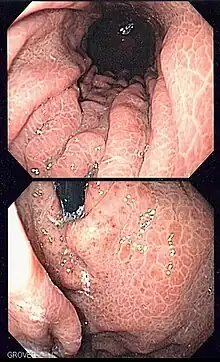

Image of portal hypertensive gastropathy seen on endoscopy of the stomach. The normally smooth mucosa of the stomach has developed a mosaic like appearance, that resembles snake-skin. | |

Portal hypertensive gastropathy refers to changes in the mucosa of the stomach in patients with portal hypertension; by far the most common cause of this is cirrhosis of the liver. These changes in the mucosa include friability of the mucosa and the presence of ectatic blood vessels at the surface. Patients with portal hypertensive gastropathy may experience bleeding from the stomach, which may uncommonly manifest itself in vomiting blood or melena; however, portal hypertension may cause several other more common sources of upper gastrointestinal bleeding, such as esophageal varices and gastric varices. On endoscopic evaluation of the stomach, this condition shows a characteristic mosaic or "snake-skin" appearance to the mucosa of the stomach.

The diagnosis of portal hypertensive gastropathy is usually made on endoscopy. The usual appearance of portal hypertensive gastropathy on endoscopy is a mosaic-like or reticular pattern in the mucosa. Red spots may or may not be present. The pattern is usually seen throughout the stomach.[2] A similar pattern can be seen with a related condition called gastric antral vascular ectasia (GAVE), or watermelon stomach. However, in GAVE, the ectatic blood vessels are more commonly found in the antrum or lower part of the stomach.[2]